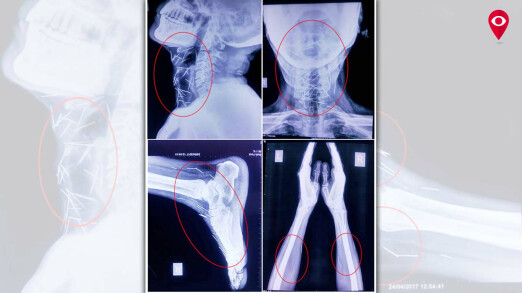

राजस्थानच्या बुंदी तालुक्यातील महिपुरा बस्ती येथे राहणाऱ्या बद्रीलाल यांच्या शरीरात जवळपास 75 पेक्षा जास्त टाचण्या असल्याचं समोर आलं आहे. 56 वर्षीय बद्रीलाल आठवड्यापूर्वी मुंबईच्या जगजीवन राम हॉस्पिटलमध्ये दाखल झाले आहेत. त्यांच्यावर उपचार करणाऱ्या डॉक्टरांचं म्हणणं आहे की, या टाचण्या फक्त शस्त्रक्रियेद्वारेच काढता येऊ शकतील. बद्रीलाल यांच्या घशाच्या भागात अंदाजे 40 पीन्स आहेत. तसंच, हात आणि पायांमध्येही टाचण्या आढळून आल्या आहेत. ही एक असाधारण केस असल्याचं डॉक्टरांचं म्हणणं आहे.

बद्रीलाल पश्चिम मार्गावरील ट्रेनसाठी पाणी सोडण्याचं काम करतात. एक्स-रेच्या अहवालानुसार, त्यांच्या शरीरात 75 टाचण्या आढळून आल्या आहेत. ज्यामुळे त्यांना 'टाचण्या खाणारी व्यक्ती’ असं नाव देण्यात आलं आहे. बद्रीलाल यांना राजस्थानमधील कोटा इथल्या एका रुग्णालयातून मुंबईतल्या रुग्णालयात पाठविण्यात आले. त्यांच्या शरीरात सुमारे 75 टाचण्या आहेत. मान आणि वरच्या छातीमध्ये 40 टाचण्या आहेत. त्यांच्या उजव्या पायात 25 आणि उजव्या आणि डाव्या हातात 2-2 टाचण्या आढळून आल्या आहेत.

बद्रीलालला काहीच आठवत नाही. त्यामुळे नेमकं कारण कळू शकलेलं नाही. याविषयी तज्ज्ञांशी बोलून पुढे काय उपचार द्यायचे ते ठरवणार आहोत. आम्ही बद्रीलाल यांना खूप प्रश्न विचारले पण त्यांनी काहीच उत्तरं दिली नाही. मग, आम्ही त्यांची चौकशी करून त्यांच्या काही टेस्ट केल्या. त्यानंतर त्यांच्या शरीरात असणाऱ्या टाचण्या दिसून आल्या. घशात दिसलेल्या टाचण्या काढण्यासाठी मोठी मेहनत घ्यावी लागेल. बद्रीलाल यांच्या अनेक तपासण्या करण्यात आल्या. त्यांच्या गळ्याचा एक्स-रे ज्यावेळेस काढला तेव्हा अनेक टाचण्या त्यांच्या घशात आढळून आल्या. त्यानंतर त्यांच्या घशाचा, छातीचा, दोन्ही हातांचा, दोन्ही पायांचा एक्स-रे काढला गेला. त्या एक्स-रे मध्ये भरपूर टाचण्या आढळून आल्या. त्यांच्या शरीरात असलेल्या टाचण्या शस्त्रक्रियेद्वारेच काढता येतील. त्यासाठी इएनटी आणि छातीच्या विशेष तज्ञ्जांची मदत घेतली जाईल. बद्रीलाल यांच्या शरीरातून या टाचण्या काढणं हे आव्हान आहे.